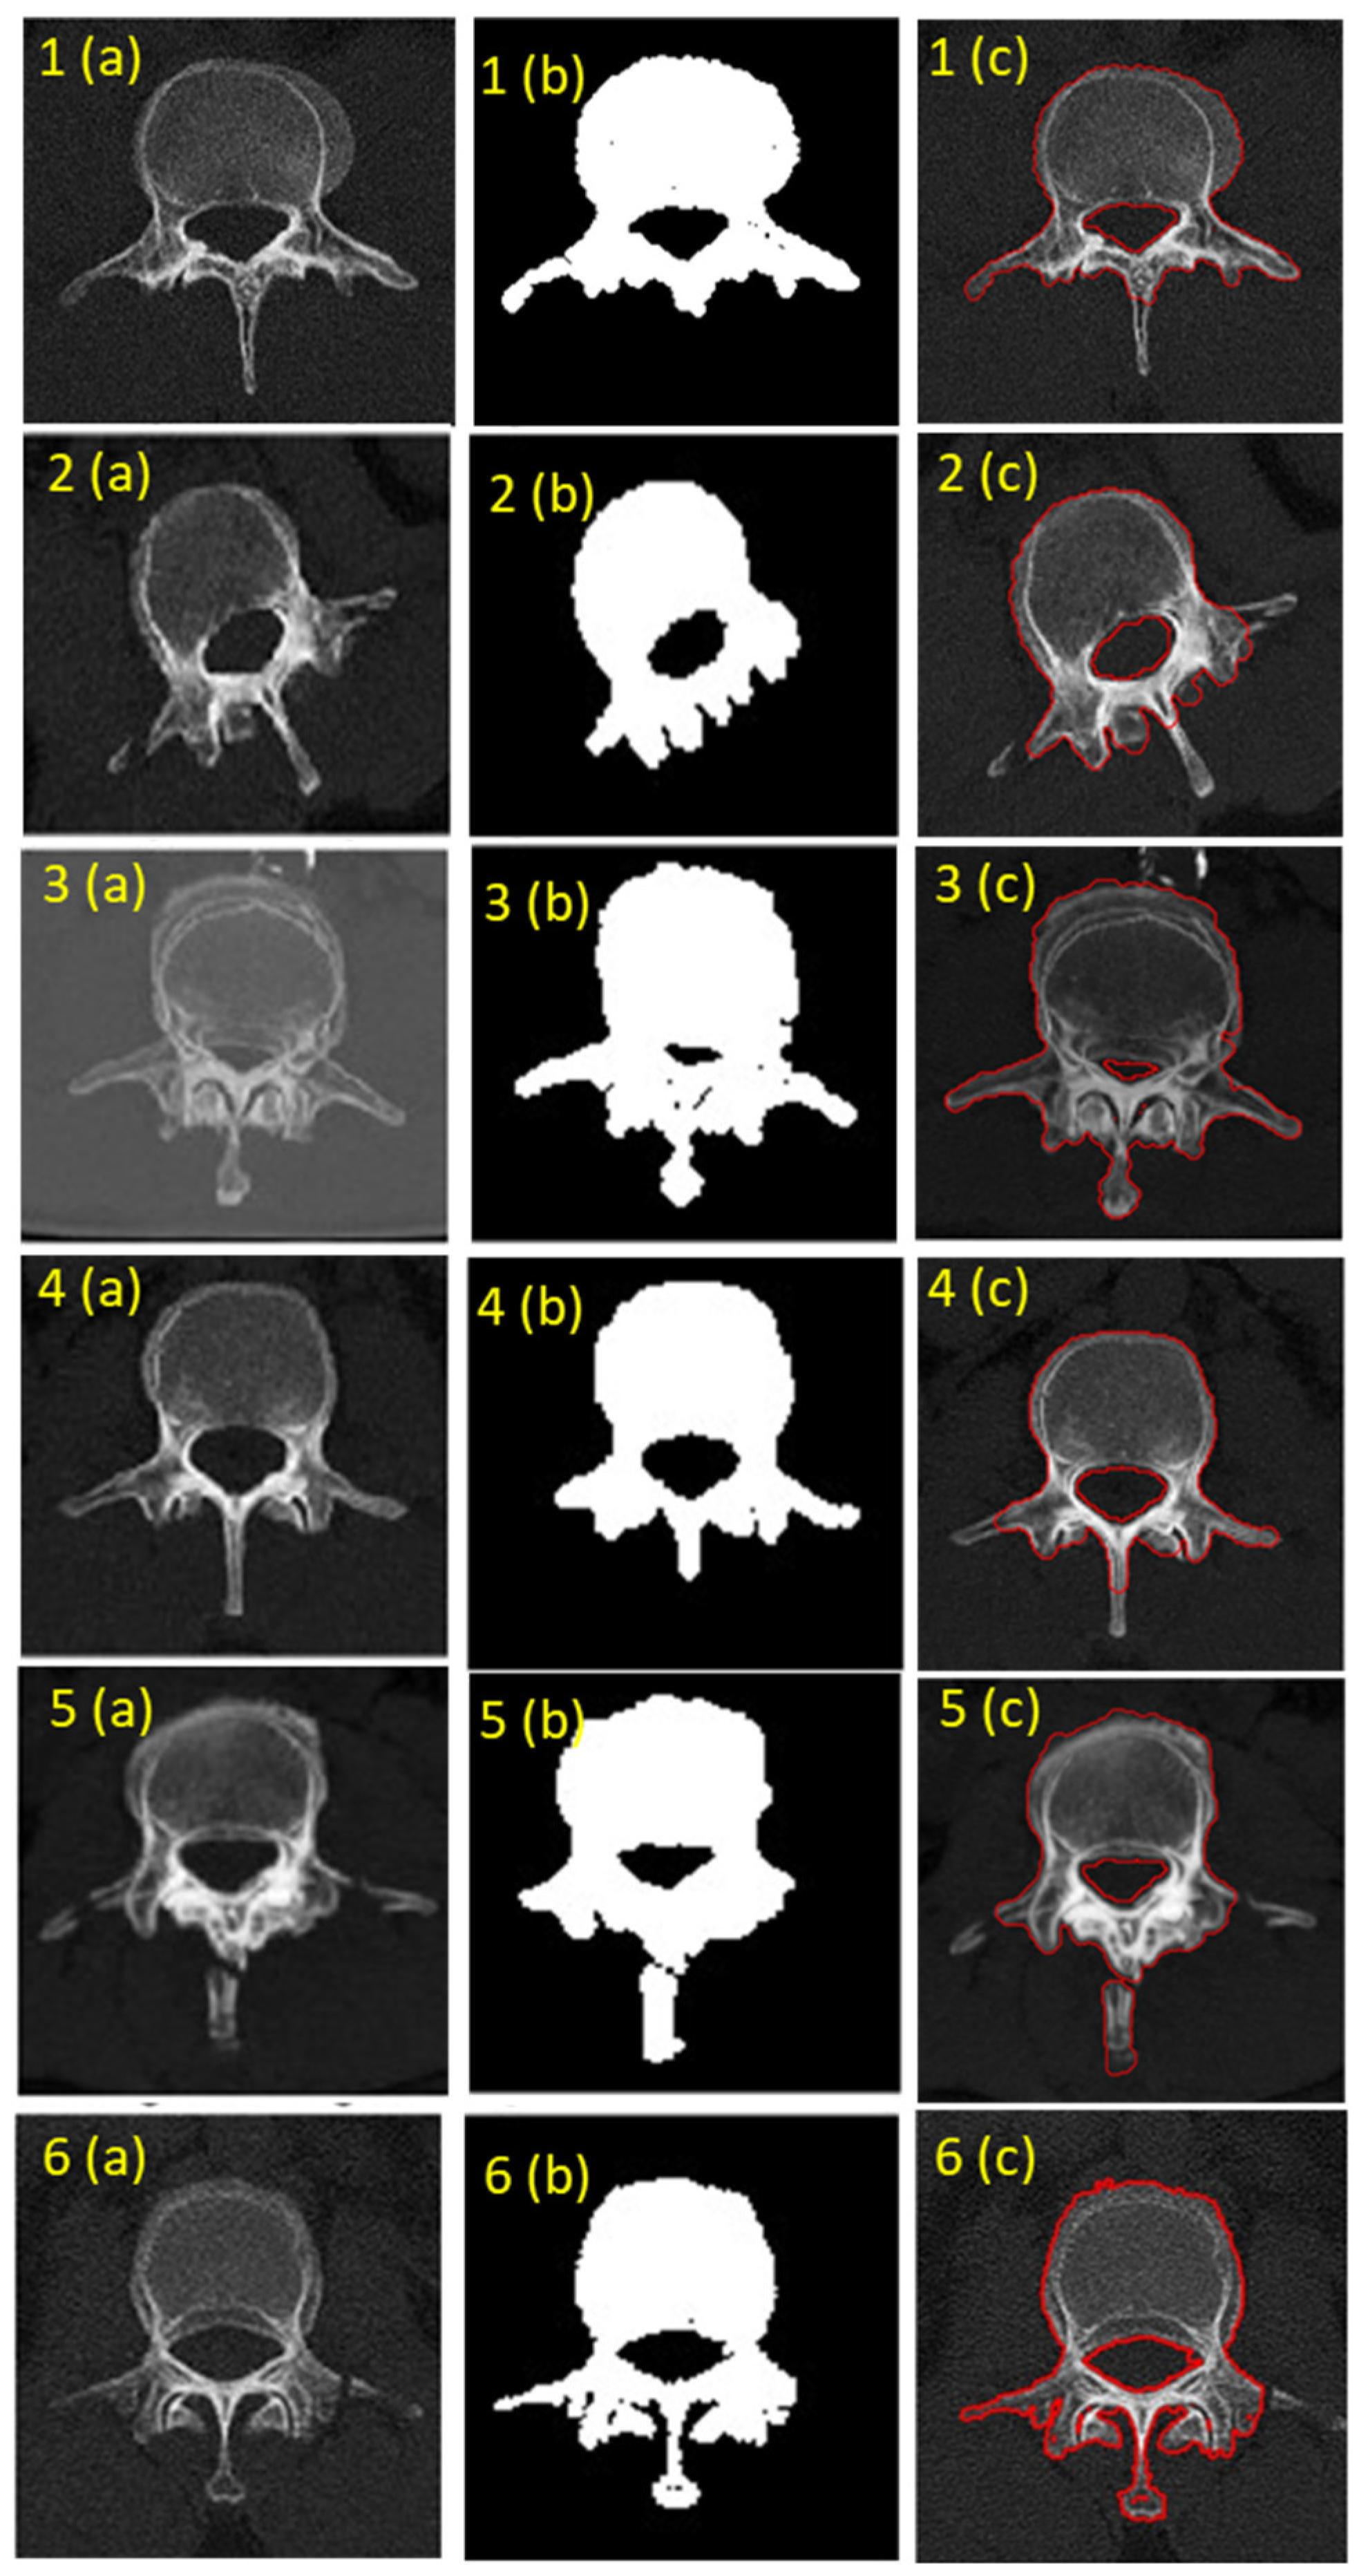

Feature extraction from the lumbar vertebrae CT scans was conducted using Otsu’s method is an effective thresholding technique that separates the foreground (vertebrae) from the background by maximizing the between-class variance, as shown in Figure 7. The process involved computing the histogram of pixel intensities from the CT images determining the probabilities of the background and foreground classes, computing cumulative sums and means calculating the between-class variance for each possible threshold selecting, the threshold that maximizes the between-class variance and applying the optimal threshold to create a binary mask segmenting the vertebrae from the surrounding tissue. This feature extraction process ensures that the chosen threshold maximizes the distinction between the two classes enhancing the accuracy of segmentation. The final results of segmentation are shown in Figure 8. The 3D figure surface has been smoothened by using the 3D editor tool Autodesk for fine finish.

Figure 7. Vertebra feature extraction using Otsu’s method. (a) CT scan image (b). Segmented binary mask. (c) CT image with segmented contour.